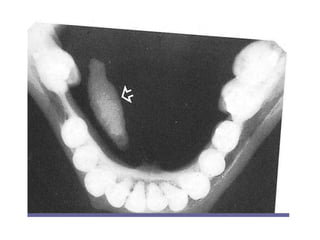

• Intraorally a calcified deposit may be seen at the

• Radiography is helpful in confirming the diagnosis and

• However, not all calculi are radiopaque and therefore

mucous plugs, may be required.